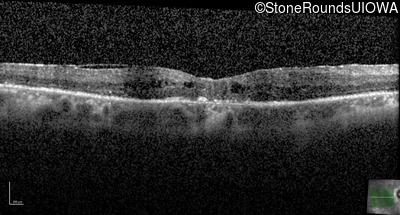

Age at visit: 66 years

OD OS

Age at visit: 67 years